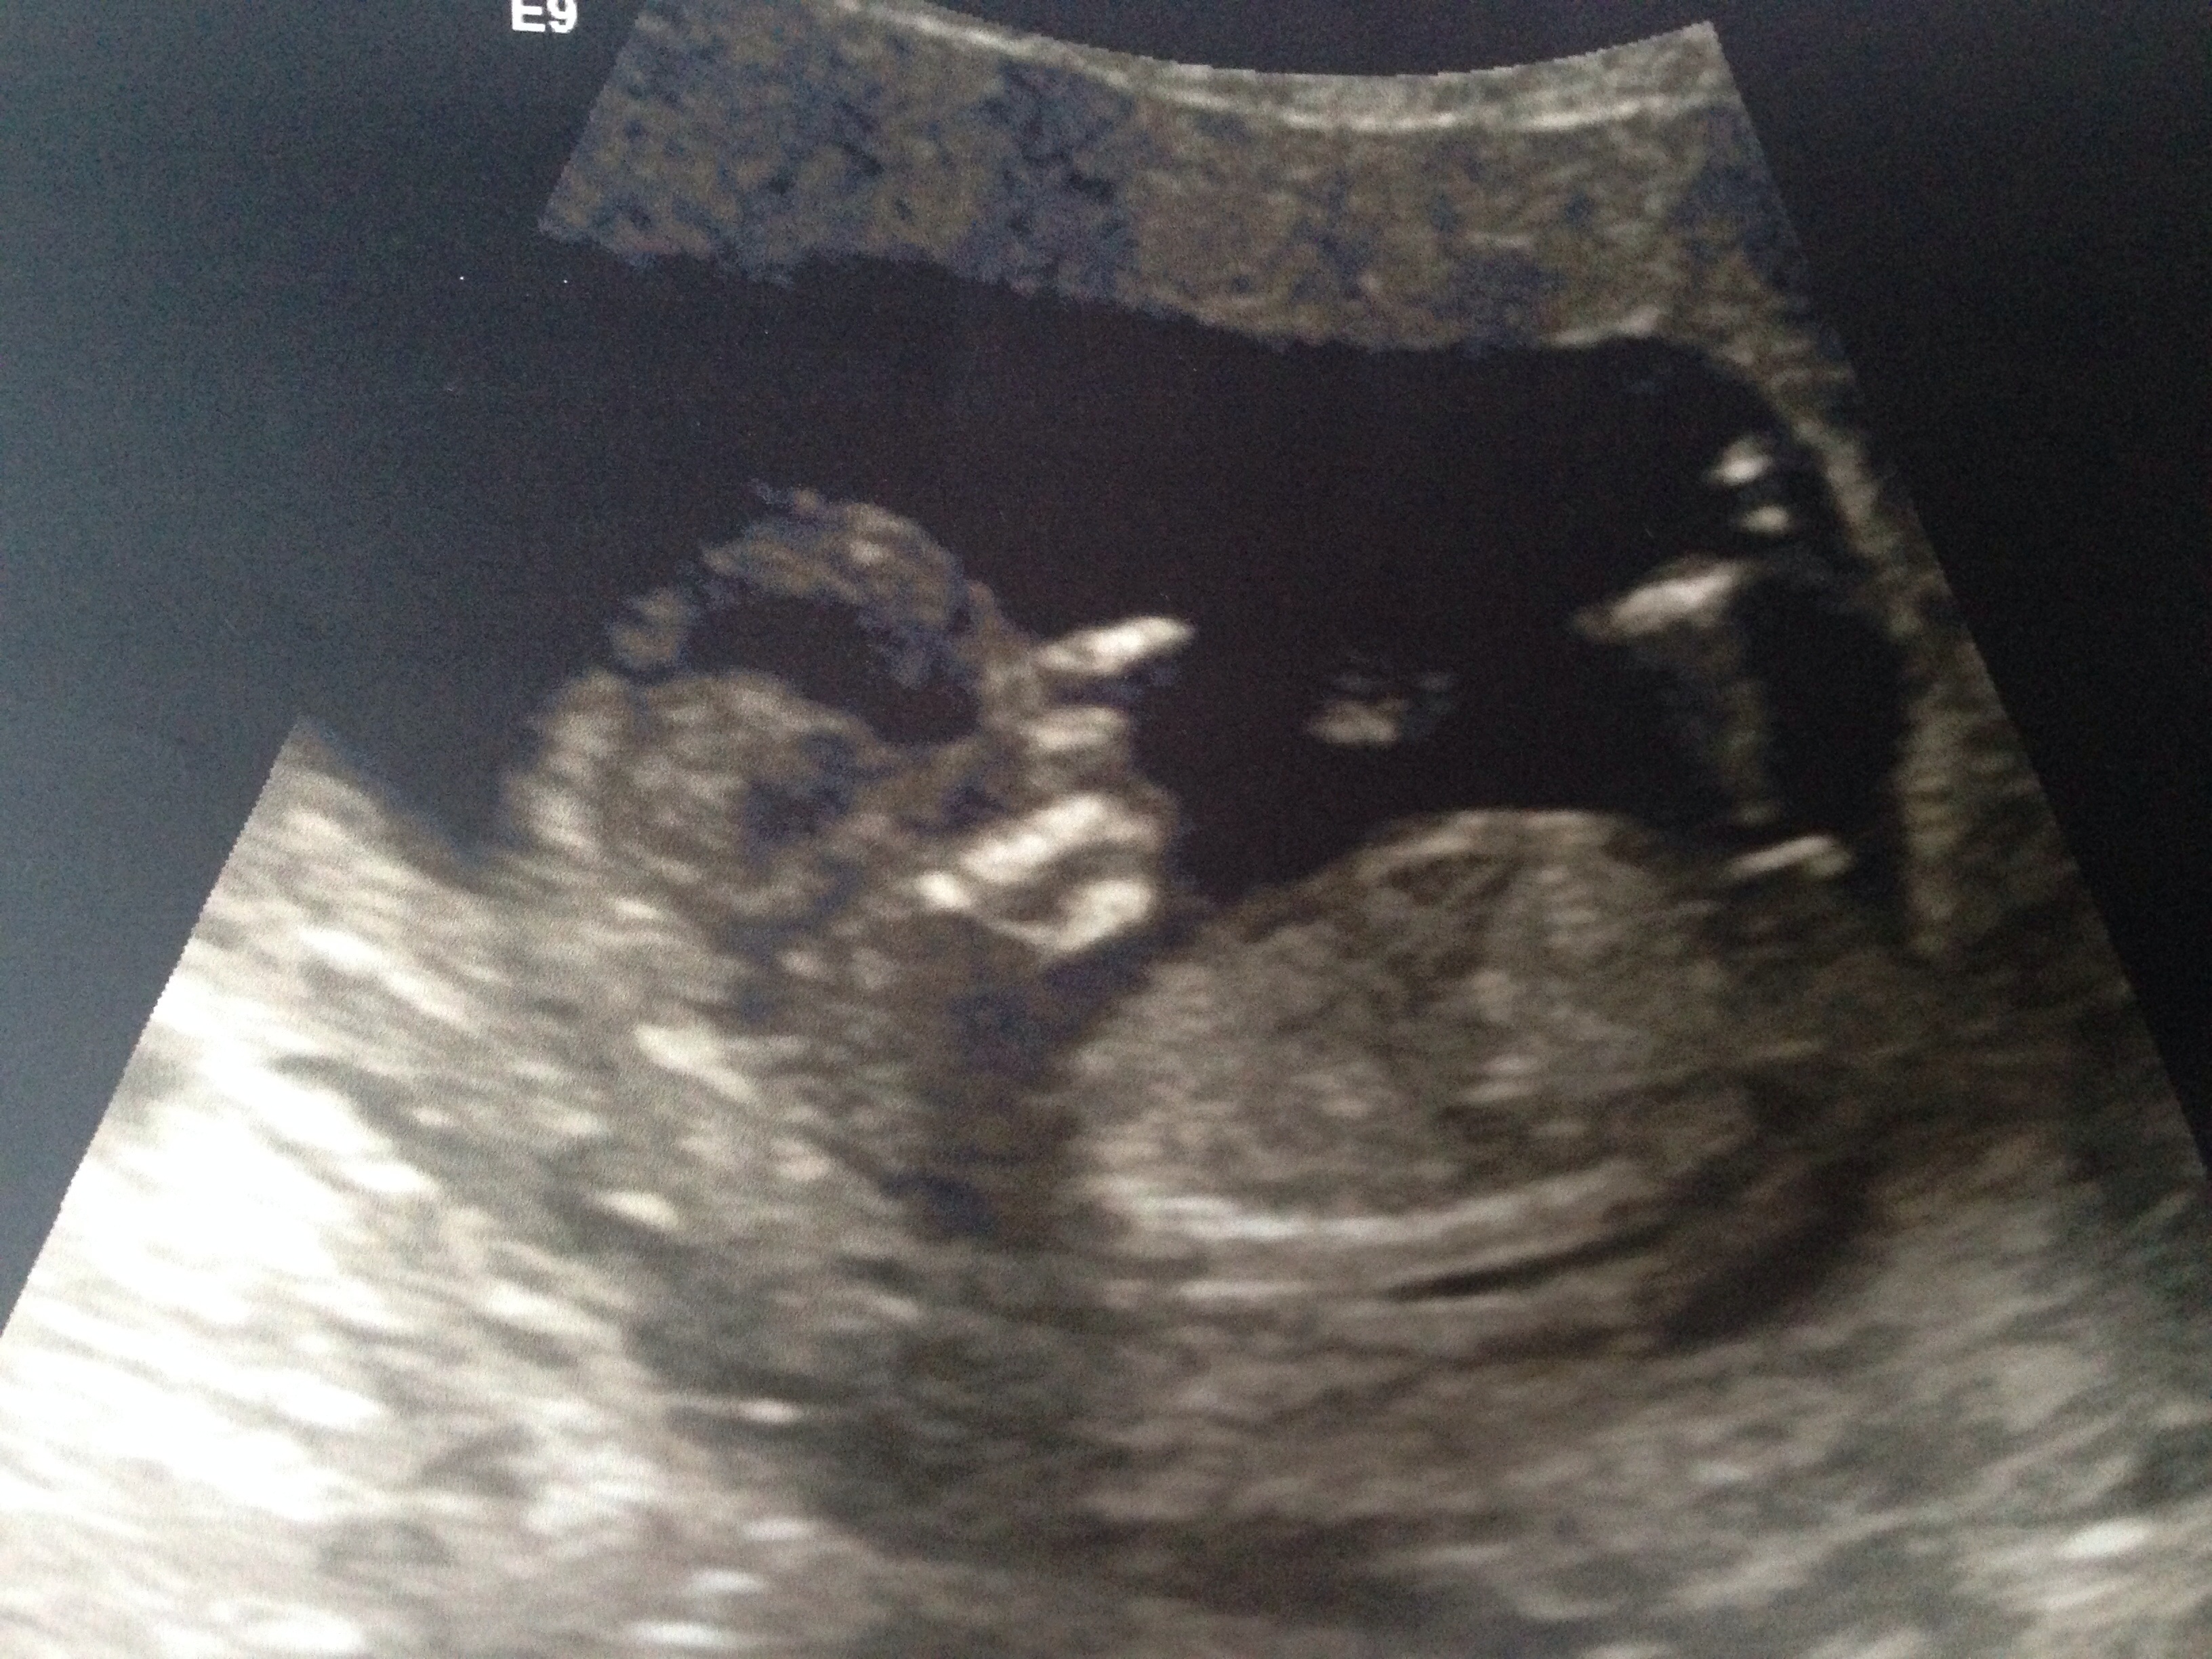

Hey I'm now 13 weeks 3 days these pics are from 13+1 can you predict gender I already have two boys looking at the nub I can't tellAttachment 16021Attachment 16022

Leaning girl. Congrats!

No nub in top pic but I would say girl from the bottom pic :) congrats!

Boy skull but girlie nub!

Looks girlie congrats x

Girl nub.

Looks like a pink bundle :)